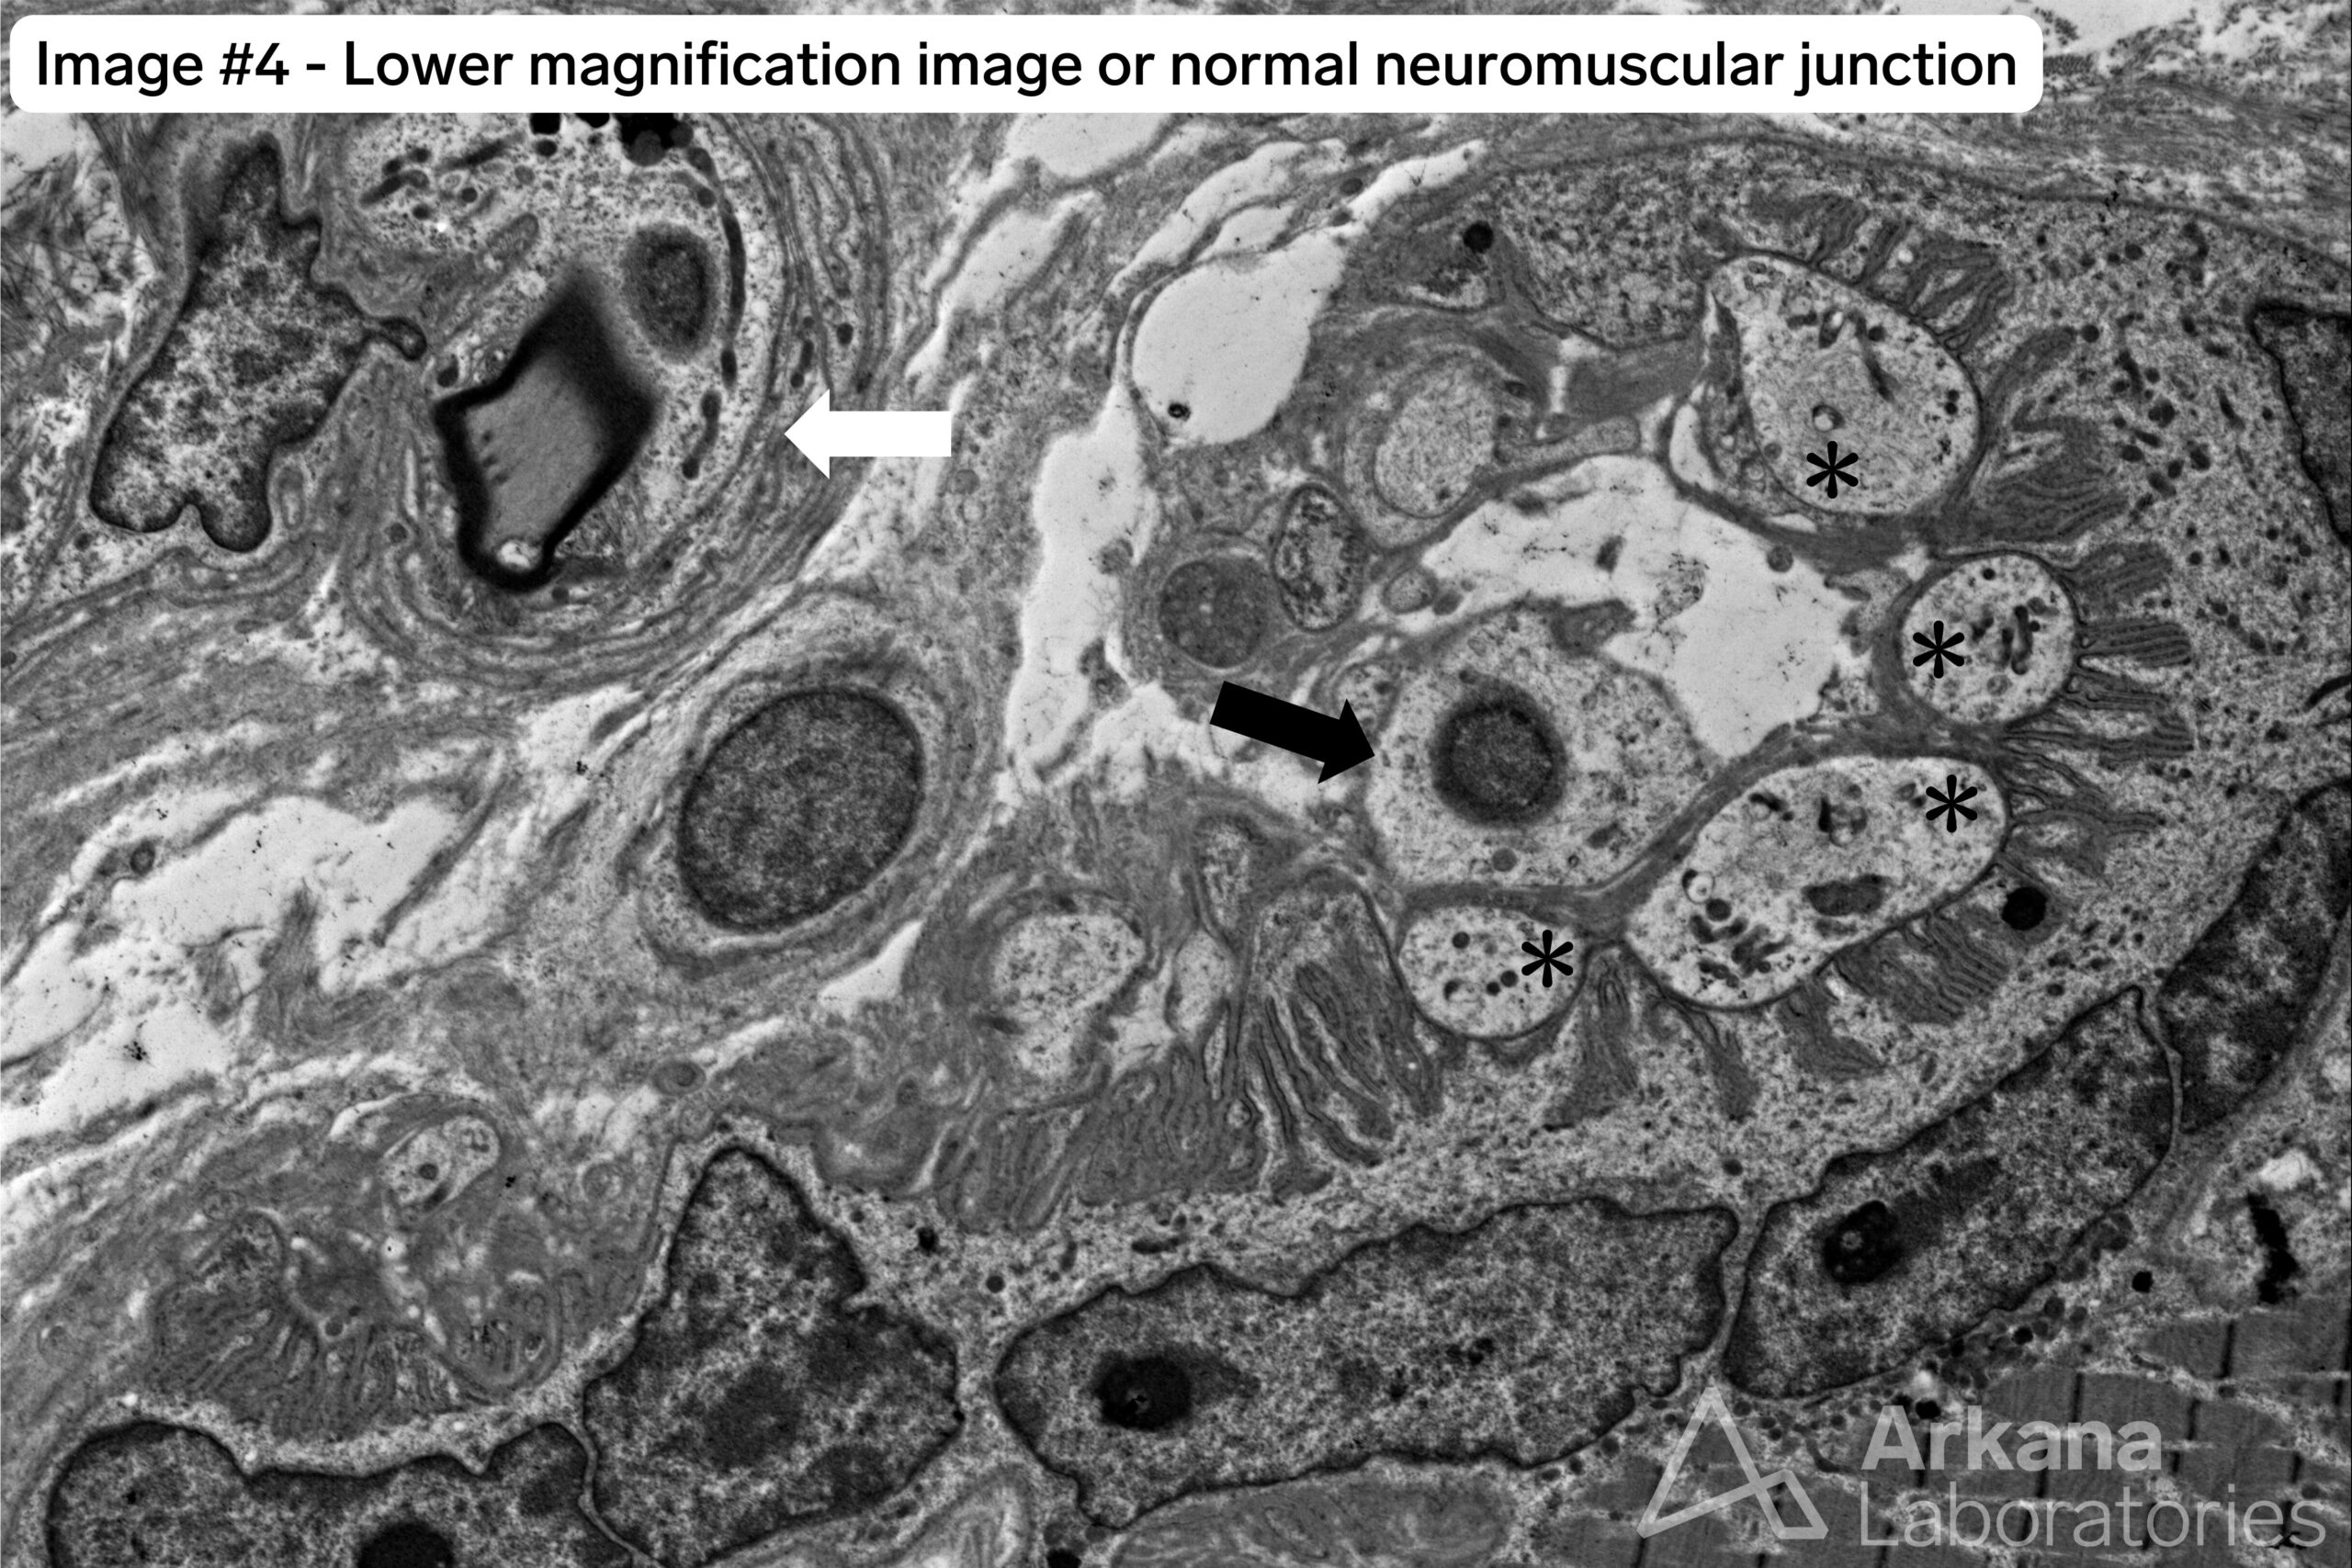

For comparison, image #4 is from a normal neuromuscular junction.

Image #4 of a normal NMJ shows the following:

- White arrow: small intramuscular nerve twig. The presence of these in a tissue section indicates the likely presence of NMJs in the vicinity.

- Black arrow: terminal Schwann cell.

- Asterisks symbol (*): terminal motor axon bouton. Note that these are not myelinated. Also note the adjacent motor end plate which represents a specialized area of the muscle fiber cell membrane (sarcolemma) which shows an undulating appearance due to extensive folding (junctional folds). The motor end plate is narrowly separated from the terminal axon bouton by a thin space known as the synaptic cleft.